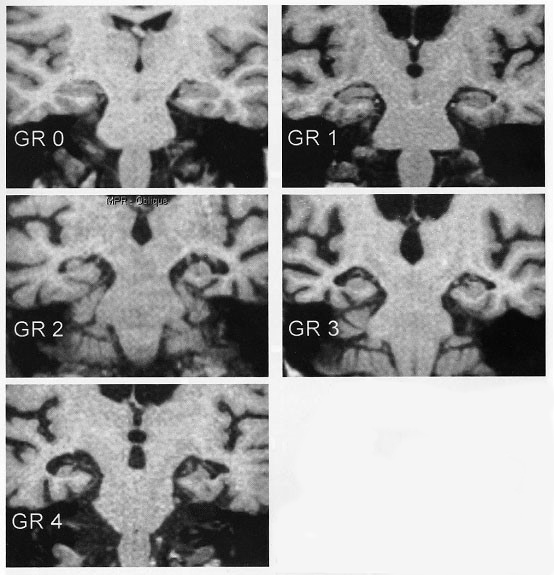

Scheltensin luokitus «Scheltens P, Launer LJ, Barkhof F ym. Visual asses...»1 hippokampusatrofian (MTA) asteen arvioimiseksi

Scheltensin viisiportaista luokittelua «Scheltens P, Launer LJ, Barkhof F ym. Visual asses...»1 käytetään luokittelemaan visuaalisesti temporomesiaalialueen atrofian astetta, erityisesti hippokampusatrofiaa.

Lähde: Valk J, Barkhof F, Scheltens P. Magnetic Resonance in Dementia. Springer-Verlag, 2002. © Philip Scheltens